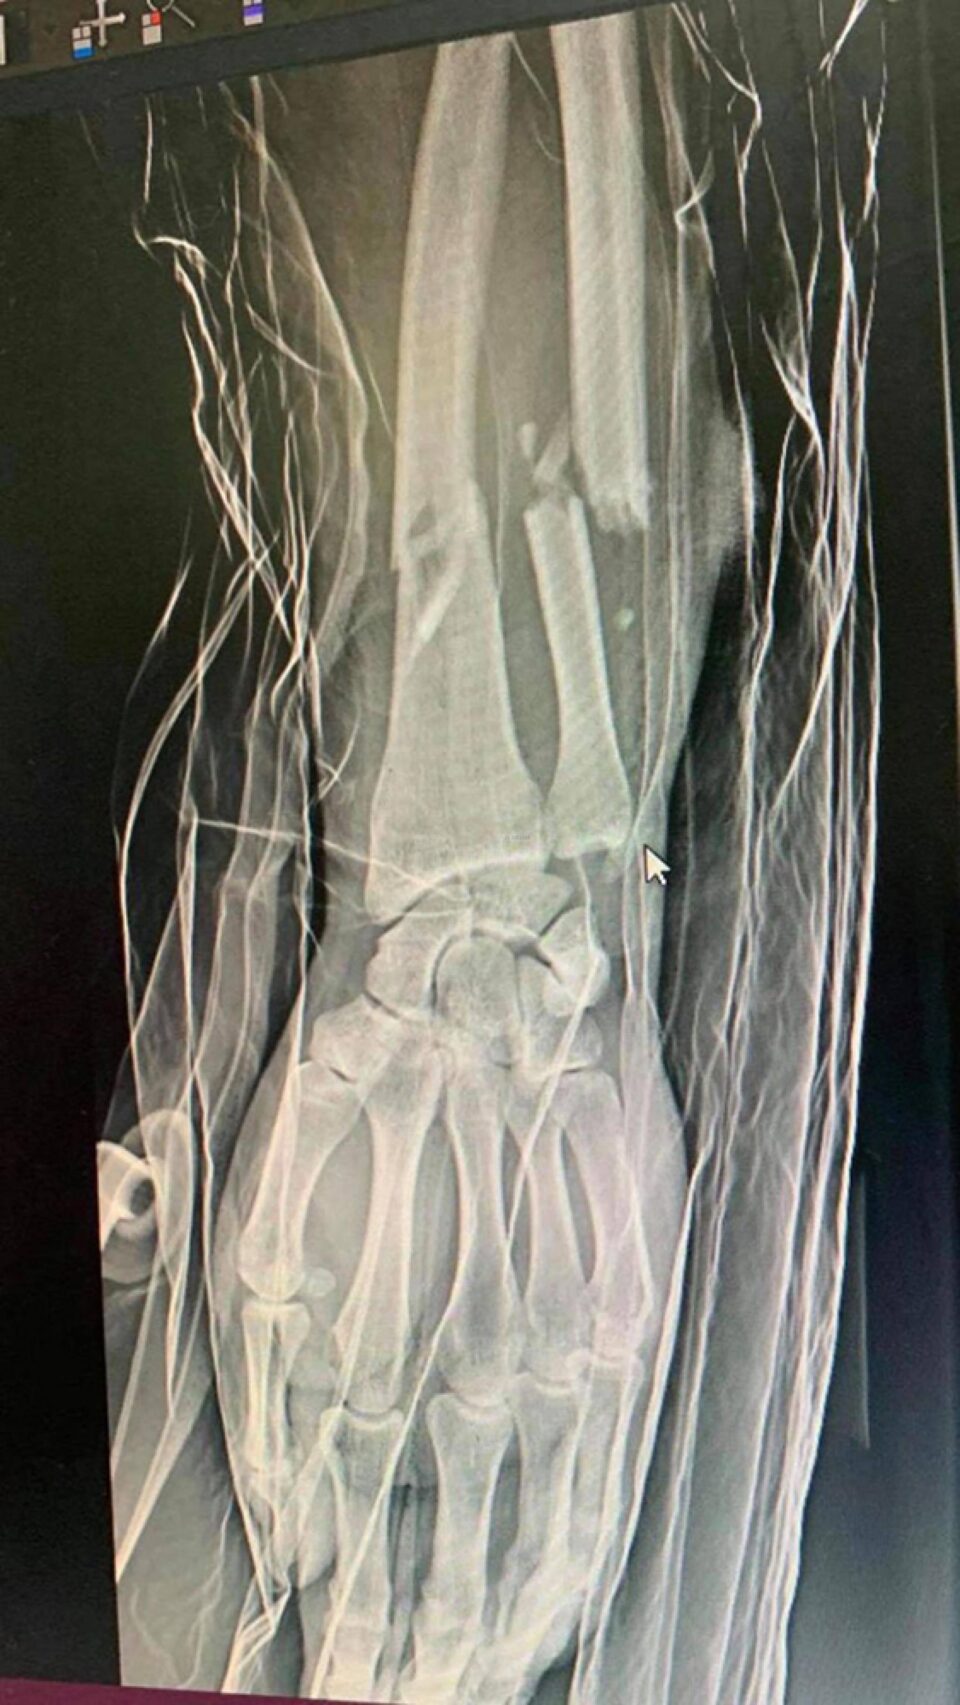

În zona denumită „Carahula”, în Straja, tânărul, care se deplasa cu un VW Touran, din direcția Vicovu de Sus spre comuna Brodina, a fost blocat de două mașini. Tânărul a fost lovit violent în cap și spune că și-a salvat viața doar pentru că a parat o parte din lovituri cu brațul. Despre cât de violentă a fost agresiunea, fotografiile trimise de victimă sunt elocvente. Tânărul a fost operat la Spitalul Județean Suceava, pentru suturarea unei plăci adânci la cap. De asemenea, acestuia i-a fost fracturat brațul în timpul agresiunii, cel cu care a parat o parte din loviturile cu bâtele.